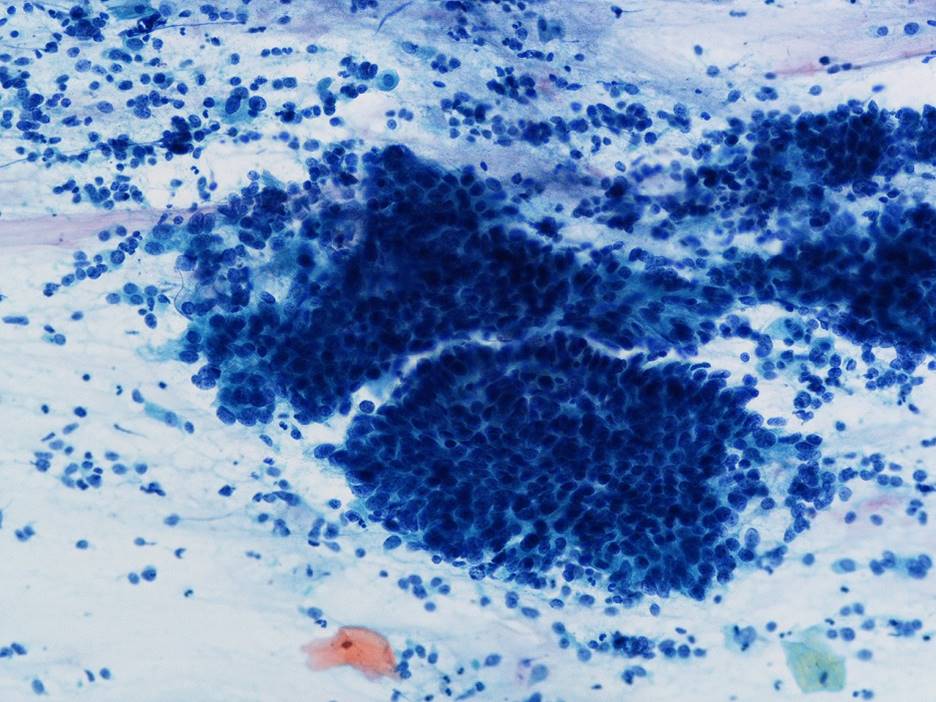

細胞診所見

背景に壊死物質は認められなかった。その中に偏在性核で核クロマチン増量を示す腺系異型細胞の不整形集塊を認めた。柵状配列や腺管構造もみられ上皮内腺癌を疑う細胞と考えた。またN/C比が高く細顆粒状の核クロマチンを有する傍基底型核異常を疑う細胞もみられた

[まとめ] 稀な子宮頸部腫瘍の症例を経験した。細胞診スメア標本では2種類の異なる異型細胞を認識することはできたがLBC標本では難しく神経内分泌癌との推定には至らなかった。腺系病変を疑う症例では、異なる成分の混在を念頭に注意深く鏡検することが重要と考えた。

[まとめ] 稀な子宮頸部腫瘍の症例を経験した。細胞診スメア標本では2種類の異なる異型細胞を認識することはできたがLBC標本では難しく神経内分泌癌との推定には至らなかった。腺系病変を疑う症例では、異なる成分の混在を念頭に注意深く鏡検することが重要と考えた。